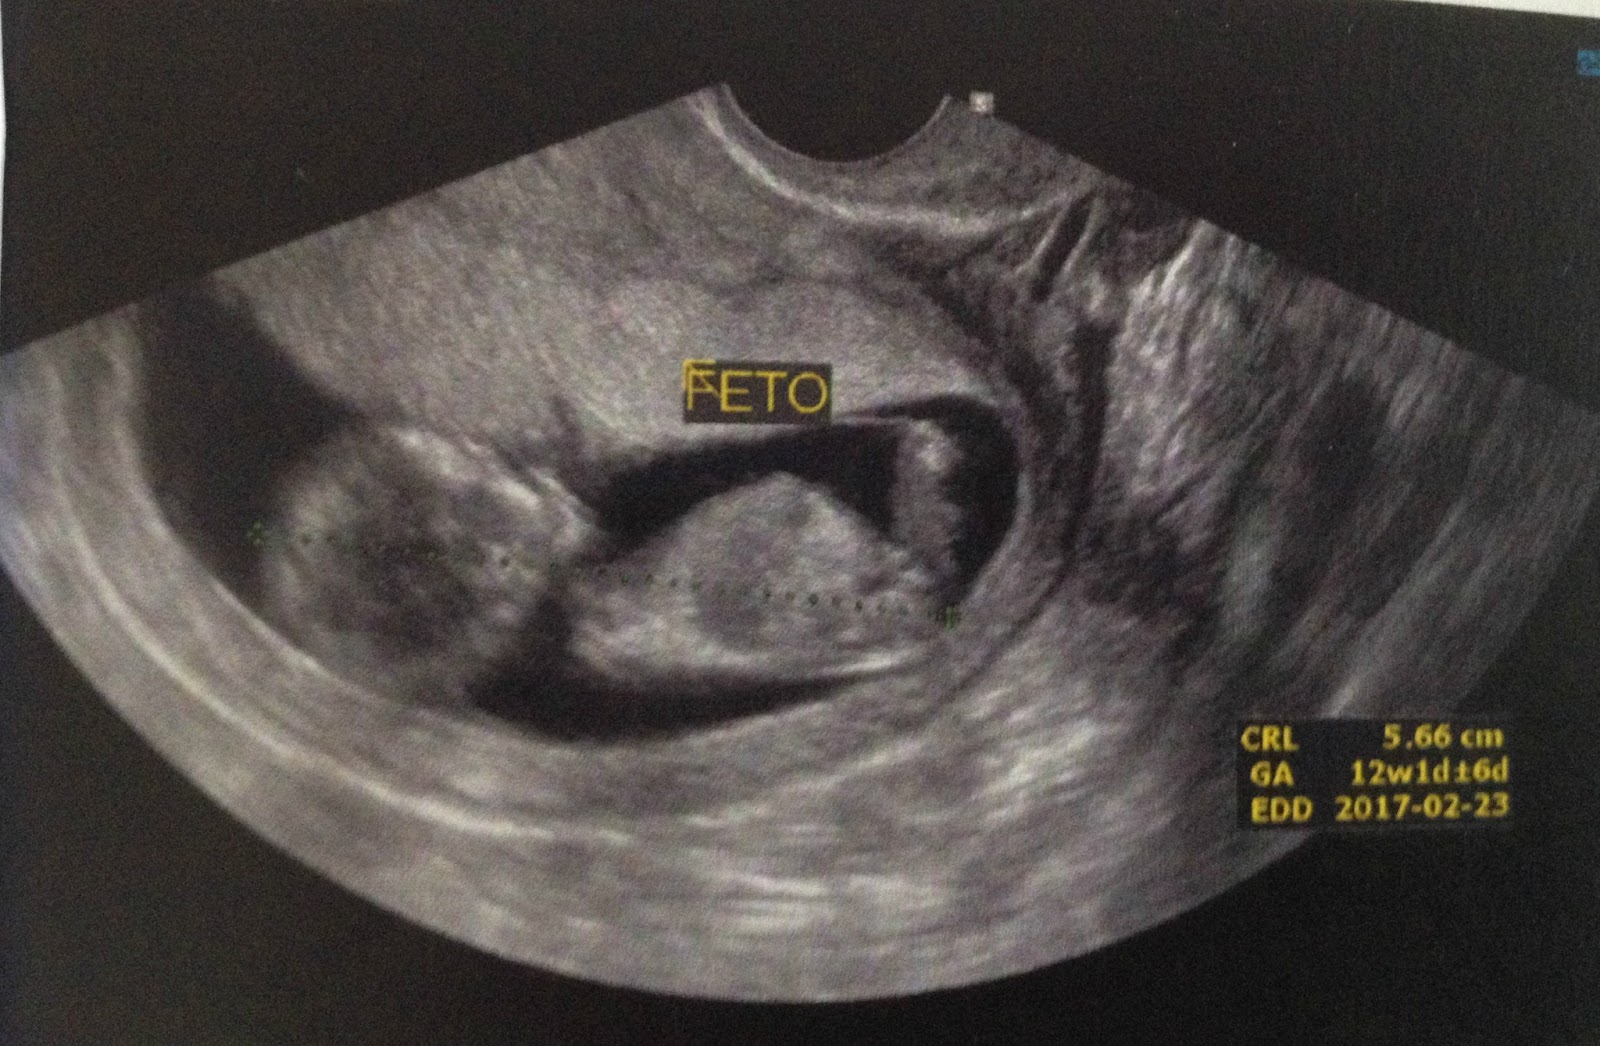

Com 12 semanas é quando se faz à Translucência nucal um exame bem importante que pode detecta anomalias e doenças no bebê, confesso que fiquei alguns dias sem dormir por conta desse exame, mas graças à Deus tudo correu bem, nesse exame o médico também consegue dar um chute sobre o sexo, isso se você já não fez a sexagem fetal e acabou com sua ansiedade.

Nós optamos por não fazer, acho que todo esse sentimento de que minha ficha ainda não caiu sobre eu estar de fato grávida me fez não ser tão ansiosa quanto eu achei que seria, não me arrependo nem um pouco de não ter feito o exame, o médico deu um chute no exame da TN de que seria um menino,e é o Santiago óbvio ficou em êxtase, eu idem pois sempre quis fosse menino.